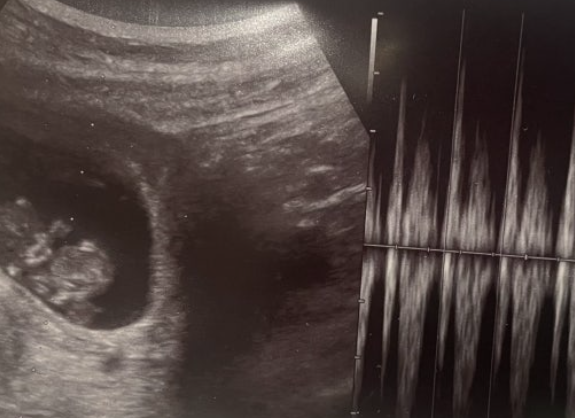

์์ ์ด๊ธฐ์ ํ์์ ๊ฑด๊ฐ ์ํ๋ฅผ ํ์ธํ๋ NIPT(๋น์นจ์ต์ ์ฐ์ ๊ฒ์ฌ)๋ ์ผ๋ฐ์ ์ผ๋ก ์์ 10์ฃผ ์ดํ๋ถํฐ ๊ฐ๋ฅํฉ๋๋ค. ์ด๋ ์ด ์๊ธฐ๊ฐ ๋์ด์ผ ํ์ DNA๊ฐ ์ฐ๋ชจ ํ์ก์ ์ถฉ๋ถํ ์กด์ฌํ๊ธฐ ๋๋ฌธ์ ๋๋ค.

NIPT ๊ฒ์ฌ๋ ํนํ ๊ณ ์ํ๊ตฐ ์์ฐ๋ถ(35์ธ ์ด์, ์ผ์์ฒด ์ด์ ํ์ ์์ ๊ฒฝ๋ ฅ์, ์ด์ํ ์ด์ ์๊ฒฌ์ ๋ฑ)์๊ฒ ์์ 10-12์ฃผ ์ฌ์ด์ ๊ถ์ฅ๋ฉ๋๋ค. ์กฐ๊ธฐ ๊ฒ์ฌ๋ฅผ ํตํด ์์ ๊ด๋ฆฌ ๊ณํ์ ๋น ๋ฅด๊ฒ ์๋ฆฝํ ์ ์๋ค๋ ์ฅ์ ์ด ์์ต๋๋ค.

NIPT๋ ์ ๋ณ ๊ฒ์ฌ์ผ๋ฟ, ํ์ง ๊ฒ์ฌ๊ฐ ์๋๋๋ค. ๊ฒ์ฌ ๊ฒฐ๊ณผ๊ฐ ์์ฑ์ผ๋ก ๋์ค๋ฉด ์์ ๊ฒ์ฌ๋ ์ต๋ชจ๋ง ๊ฒ์ฌ์ ๊ฐ์ ์ถ๊ฐ์ ์ธ ํ์ง ๊ฒ์ฌ๊ฐ ํ์ํ ์ ์์ต๋๋ค.